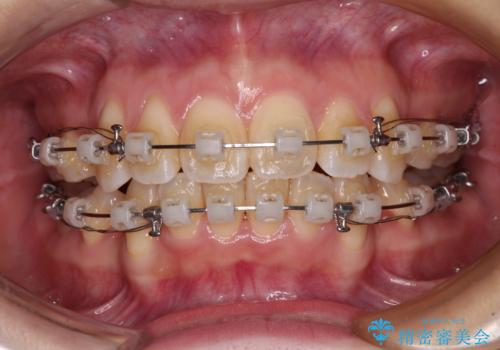

- クリアブラケット

口元を積極的に引っ込めるために、上下左右の小臼歯4本を抜歯し、目立たないワイヤー装置にて矯正治療を行うこととしました。

上下前歯の歯軸の角度が大きく改善され、お口を閉じたときに顎先に認められた梅干し様の皺も改善されました。